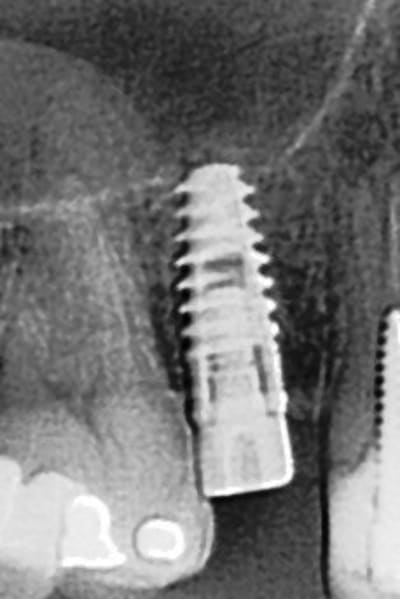

tiens...un ptit cas...

dans ce petit cas...j'ai commencé avec le kit MIS...et fini ma voie crestale avec le kit HBS...

ok, c'est un mini soulevé...mais bon , c'est un exemple...

juste une précision...premier foret 1.3mm sur 8mm...expansion pour mettre un implant de 4x10...

j'ai juste "léché" la préparation du site final avec le foret terminal du système...sur 8mm...avant d'insérer l'implant...stab primaire au top...blocage à 40 Ncm...